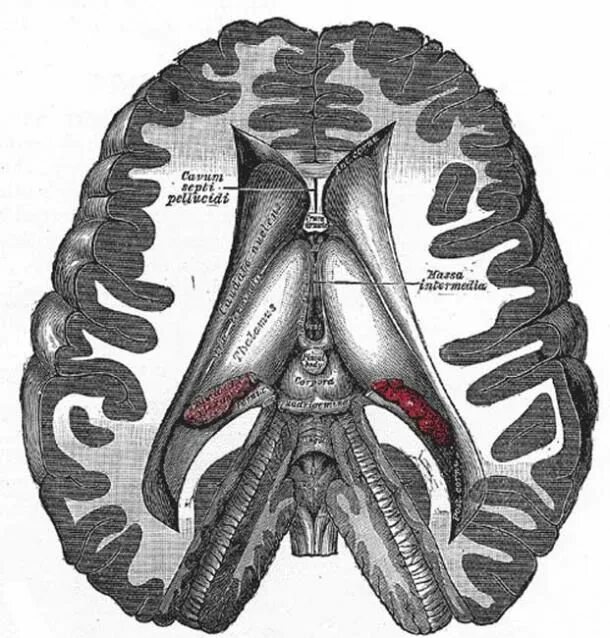

Labeled as